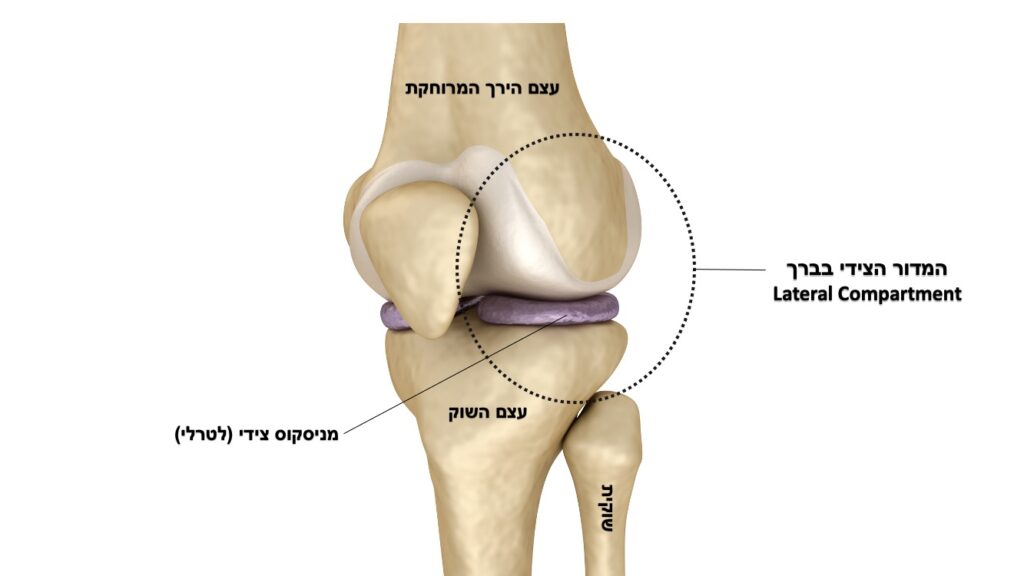

ניתוח משולב של שחזור רצועה צולבת קדמית (ACL Reconstruction) עם חיזוק צידי (אוגמנטציה לטרלית) הופך להיות יותר ויותר פופולרי בשנים האחרונות. מדובר על ניתוח משולב שנועד לתת מענה לשיעורי הכשלון הגבוהים של הניתוח הקלאסי לשחזור רצועה באוכלוסיות בסיכון ועל בסיס הידיעה שבחלק ניכר מפגיעות הרצועה הצולבת הקדמית קיימת פגיעה ברקמות חוץ-מפרקיות צידיות נוספות בברך.

אחת מהפרוצדרות הניתוחיות המקובלות ביותר כיום לחיזוק צידי היא Lateral Extra-articular ITB Tenodesis (LET) בה מפרידים חלק מה-(ITB) Ilio-Tibial Band (רצועת ירך-שוק הצידית) ומקבעים אותו לעצם הירך המרוחקת. למרות שפרוצדורה זו הפכה שכיחה בעת האחרונה, עדיין לא ברורות לחלוטין כל ההשפעות שלה על מפרק הברך בדגש על עומסים/לחצים גבוהים יותר מהנורמה שעלולים להתפתח במדור הצידי של הברך (Lateral compartment).

בעבודה זו נבדקה ההשפעה של הניתוח המשולב שכולל ביצוע חיזוק צידי (LET) בשילוב עם שחזור רצועה צולבת קדמית על העומסים והלחצים במדור הצידי של הברך בזמן תנועות סיבוביות של הברך המחקות את מנגנון הפציעה של הרצועה הצולבת הקדמית (Pivoting maneuvers).